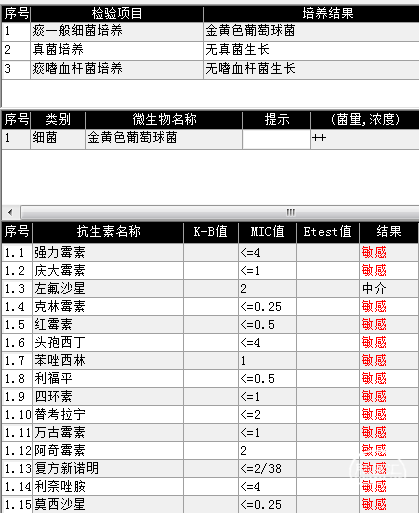

患者基本信息

患者谢某某,男性,48岁,身高175cm,体重75kg,已婚,工人,既往体健,否认药物过敏史,无家族遗传性疾病。

病史及症状描述:主诉:重型颅脑外伤术后意识障碍50天(7月30日入院);现病史:患者2023年6月11日因高处坠落伤在外地行开颅手术等治疗,病情平稳后带气管套管转回湘潭市中心医院(后续简称“我院”)治疗。

入院查体:GCS=E2VTM2=4T分,右侧瞳孔直径约4mm,对光反射迟钝,左侧瞳孔约3mm,对光放射灵敏,四肢关节被动屈伸活动无受限,四肢肌张力偏高,肌力查体无法配合,病理征未引出。

入院诊断:1. 右侧额颞部硬膜下血肿清除术后;2. 颅骨后天性缺损;3. 脑内多发软化灶形成;4. 脑积水;5. 左额骨凹陷性骨折;6. 颅底骨折;7. 左股骨干骨折内固定术后;8. 坠积性肺炎、胸腔积液;9. 气管切开术后;10. 右眼挫伤;11. 下肢肌间静脉血栓;12. 低蛋白血症。